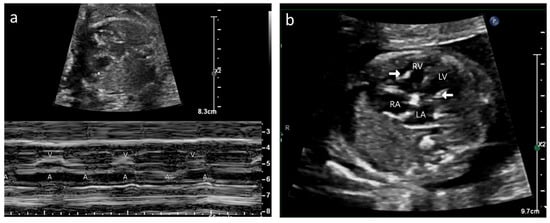

A 35-year-old G2P1 with no prior history of autoimmune disease was referred to our center at 20 + 4 weeks of gestation for fetal hydrops and bradycardia. CHB was detected in fetal echocardiography with an atrial rate of 112 bpm and a ventricular rate of 62 bpm (Figure 5a). Mild to moderate TR was present without MR. Biventricular hyperechogenicity of the papillary muscles and endocardium was noted with good coaptation of the valve leaflets (Figure 5b/Video S12). Small pericardial and pleural effusions were also noted. She was extensively investigated for hydrops, and her anti-Ro antibody titers were strongly positive with negative anti-La titers. She declined medical therapy and had her pregnancy terminated.

Figure 5.

Case B: (a) M-mode echocardiogram showing atrioventricular dissociation in the fetus. A—atrial contractions; V—ventricular contractions. (b) Echocardiogram, four-chamber view—hyperechoic papillary muscle (white arrow in RV and LV).